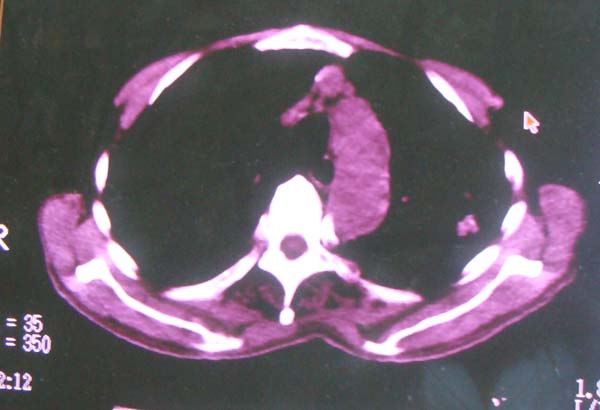

以下是引用zhangzhongshou在2008-2-15 22:25:00的发言:[br]片子照得不清,基本考虑1、细支气管肺泡癌2、亚急性血行播散型肺结核。请结合临床。片子细节显示不清,无法提供进一步意见。

以下是引用杀毒软件在2008-2-15 22:34:00的发言:[br]小叶中心性肺气肿。两肺弥漫性病变,肺泡微石病,过敏性肺炎,尘肺2期,特发性肺纤维化都有可能。[br]不象肺泡癌。